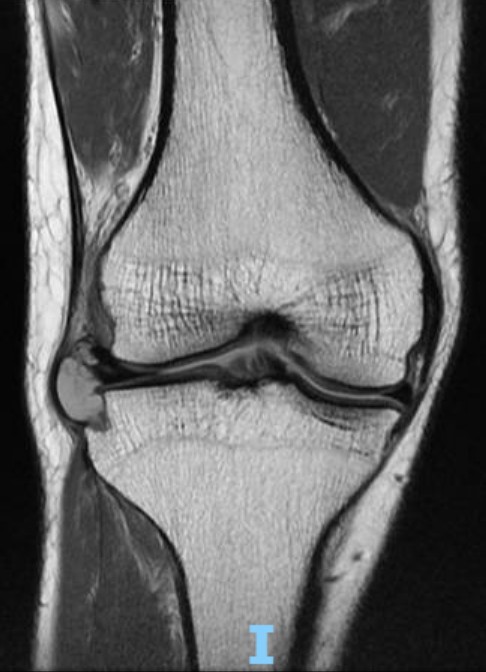

An MRI scan of his right knee was done to confirm the diagnosis.

The clinical diagnosis was a lateral meniscus horizontal cleavage tear with a large lateral meniscal cyst.